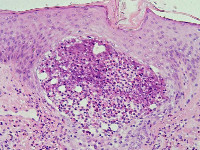

![Eosinofiele folliculitis (click on photo to enlarge) [source: www.huidziekten.nl] Eosinofiele folliculitis](../../../images/eosinofielefolliculitis1z.jpg) |

![Eosinofiele folliculitis (click on photo to enlarge) [source: www.huidziekten.nl] Eosinofiele folliculitis](../../../images/eosinofielefolliculitis2z.jpg) |

| eosinofiele

folliculitis |

eosinofiele

PA:Uitgebreid eosinofiel infiltraat, in de follikel en perifolliculair. In het klassieke geval zijn de haarfollikels ter hoogte van de inmonding v.d. talgklier (die soms ook volledig is aangetast) geïnfiltreerd met vele eosinofielen, en enkele mononucleairen en neutrofielen. Tevens bestaat spongiose en destructie van het bovenste deel van de haarfollikel (infundibulum). Ook in epidermis zonder follikels is infiltratie van eo's, met spongiose en intra-epidermale eosinofiele abcesjes. In de dermis is een perivasculair, voornamelijk eosinofiel infiltraat aanwezig.